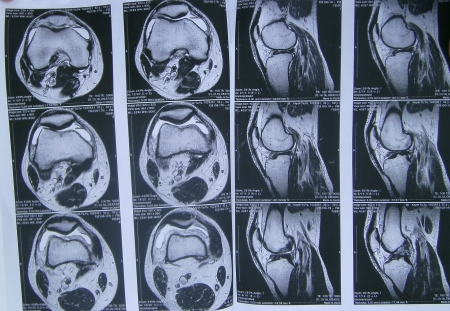

– Травму отримав, коли грали у футбол між батальйонами. Під час гри нога пішла на злам. Через три дні лікування у місцевій лікарні перевели у Миколаїв, там сказали що розірвана зв’язка та приписали знеболювальне. Приїхав додому зробив МРТ, яке показало, що у мене розрив передньої хрестоподібної зв’язки. Лікарі сказали, що на операцію необхідно 13-16 тисяч гривень залежно від курсу долара, – розповів Юрій Книш.